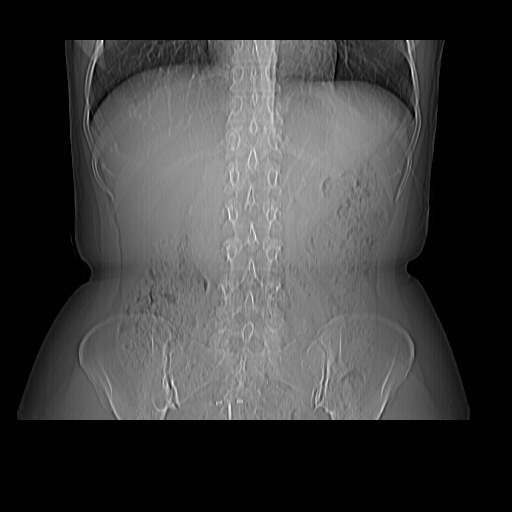

标题: CT16892:女40Y,急性阑尾住院!

女40y,急性阑尾住院!术前发现请会诊!